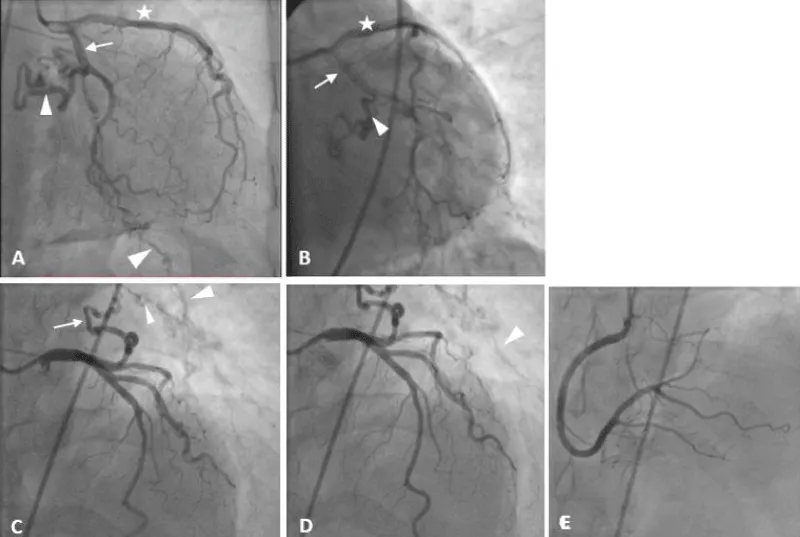

Embolization of the left circumflex coronary artery after its heart-supplying branching was done using 3 coils, and control angiography showed total occlusion of the abnormal connection, Figure 2. Total procedure time was 45 minutes and the patient discharged from the hospital without complications 24 hours later.

Figure 2: Percutaneous coronary angiography shows the anatomy of the coronary arteries. The star refers to the left anterior descending artery, the arrow refers to the left circumflex coronary artery, and the arrow head refers to the abnormal branch of the LCX that is now embolized using 3 coils.